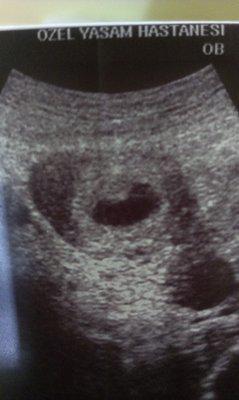

Eine leere Fruchthöhle kann bei einer Ultraschalluntersuchung festgestellt werden, wenn sich in der Gebärmutter keine Embryonalanlagen entwickelt haben. Dies wird oft als Windei bezeichnet. Es handelt sich dabei um eine Art Fehlentwicklung, bei der sich nur die äußere Zellschicht der Keimblase gebildet hat, jedoch kein Embryo vorhanden ist.

In den meisten Fällen deutet eine leere Fruchthöhle auf eine nicht intakte Schwangerschaft hin und bedeutet, dass die Schwangerschaft vorzeitig beendet werden muss. Es kann jedoch auch vorkommen, dass sich der Embryo noch nicht ausreichend entwickelt hat und daher noch nicht sichtbar ist. In solchen Fällen wird häufig zu einem späteren Zeitpunkt eine erneute Ultraschalluntersuchung durchgeführt, um das weitere Vorgehen zu bestimmen.

Wenn bei einer Ultraschalluntersuchung festgestellt wird, dass sich in der Fruchthöhle kein Embryo entwickelt hat, handelt es sich um ein Windei. Dies bedeutet, dass sich nach der Befruchtung der Eizelle zwar die äußere Zellschicht der Keimblase gebildet hat, aber die Embryonalanlagen fehlen vollständig.

Eine leere Fruchthöhle in der Ultraschalluntersuchung kann ein Anzeichen dafür sein, dass die Schwangerschaft nicht wie erwartet verläuft. Wenn bei einem positiven Schwangerschaftstest keine embryonalen Strukturen in der Fruchthöhle sichtbar sind, spricht man von einem „Windei“. Dabei hat sich zwar die äußere Zellschicht gebildet, aber es fehlen die Embryonalanlagen. In solchen Fällen kann sich die Schwangerschaft nicht weiterentwickeln.